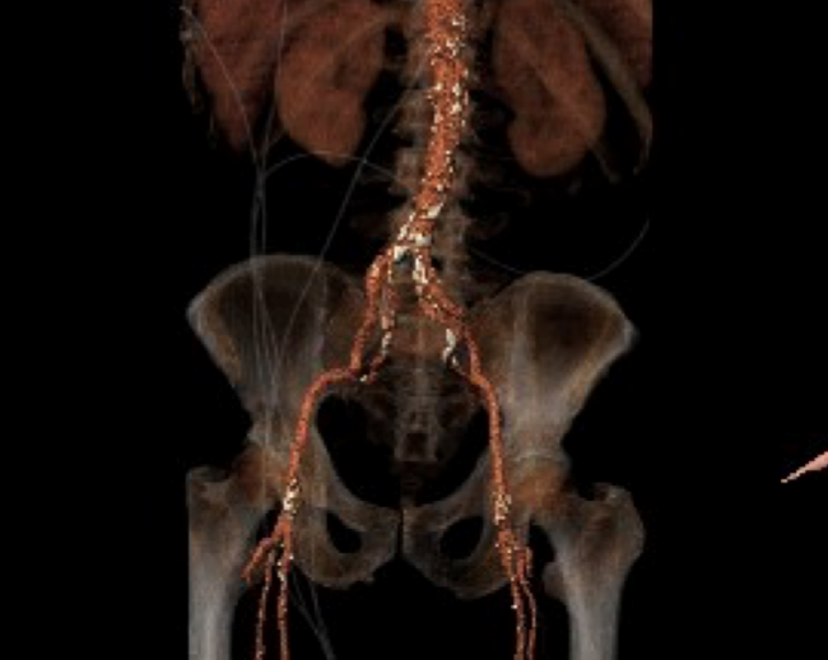

该患者为一例重度AS患者,双侧股动脉见环形钙化,外周入路挑战较大,手术风险高。主动脉瓣环水平夹角67度,横位心,假体瓣膜释放后有位移可能。

入路血管内径偏小,双侧髂总动脉血管环形钙化,内径小,存在血管夹层风险。

外周血管及主动脉弓解剖

手术过程概览

首先冠脉造影,左冠血管充盈良好,右冠近端见80%狭窄,行PCI治疗,造影显示右冠脉充盈良好。

左冠脉造影

右冠脉造影

右冠支架植入

右冠支架植入后

左股动脉切开,dsa引导下植入20Fr大鞘。行右侧猪尾导管主动脉根部造影、跨瓣。

外周造影

直头导丝跨瓣

20mm球囊预扩张,结合瓣环及术前策略,预装AV23型号瓣膜并释放至工作位。

球囊预扩

瓣膜释放至工作位

结合DSA影像,多角度观察瓣膜情况,瓣膜最终完全释放。

球囊后扩

造影评估

造影显示,因钙化原因,瓣膜贴合欠佳,行球囊后扩张,瓣膜形态佳,工作稳定,手术结束。

第三为患者同样是重度主动脉瓣狭窄合并右冠脉病变,瓣膜重度钙化,心室腔小,室壁显著增厚,入路血管不理想等一系列因素构成高难度复杂TAVR手术,为术中导丝跨瓣,加硬导丝置入左心室形态位置及瓣膜的释放带来了重重挑战。此患者同样采取PCI+TAVR一站式治疗策略,整个手术过程在团队的默契配合下顺利完成,术后即刻超声显示,主动脉瓣最大流速1.2m/s,平均压差5mmHg,血流动力学优异。